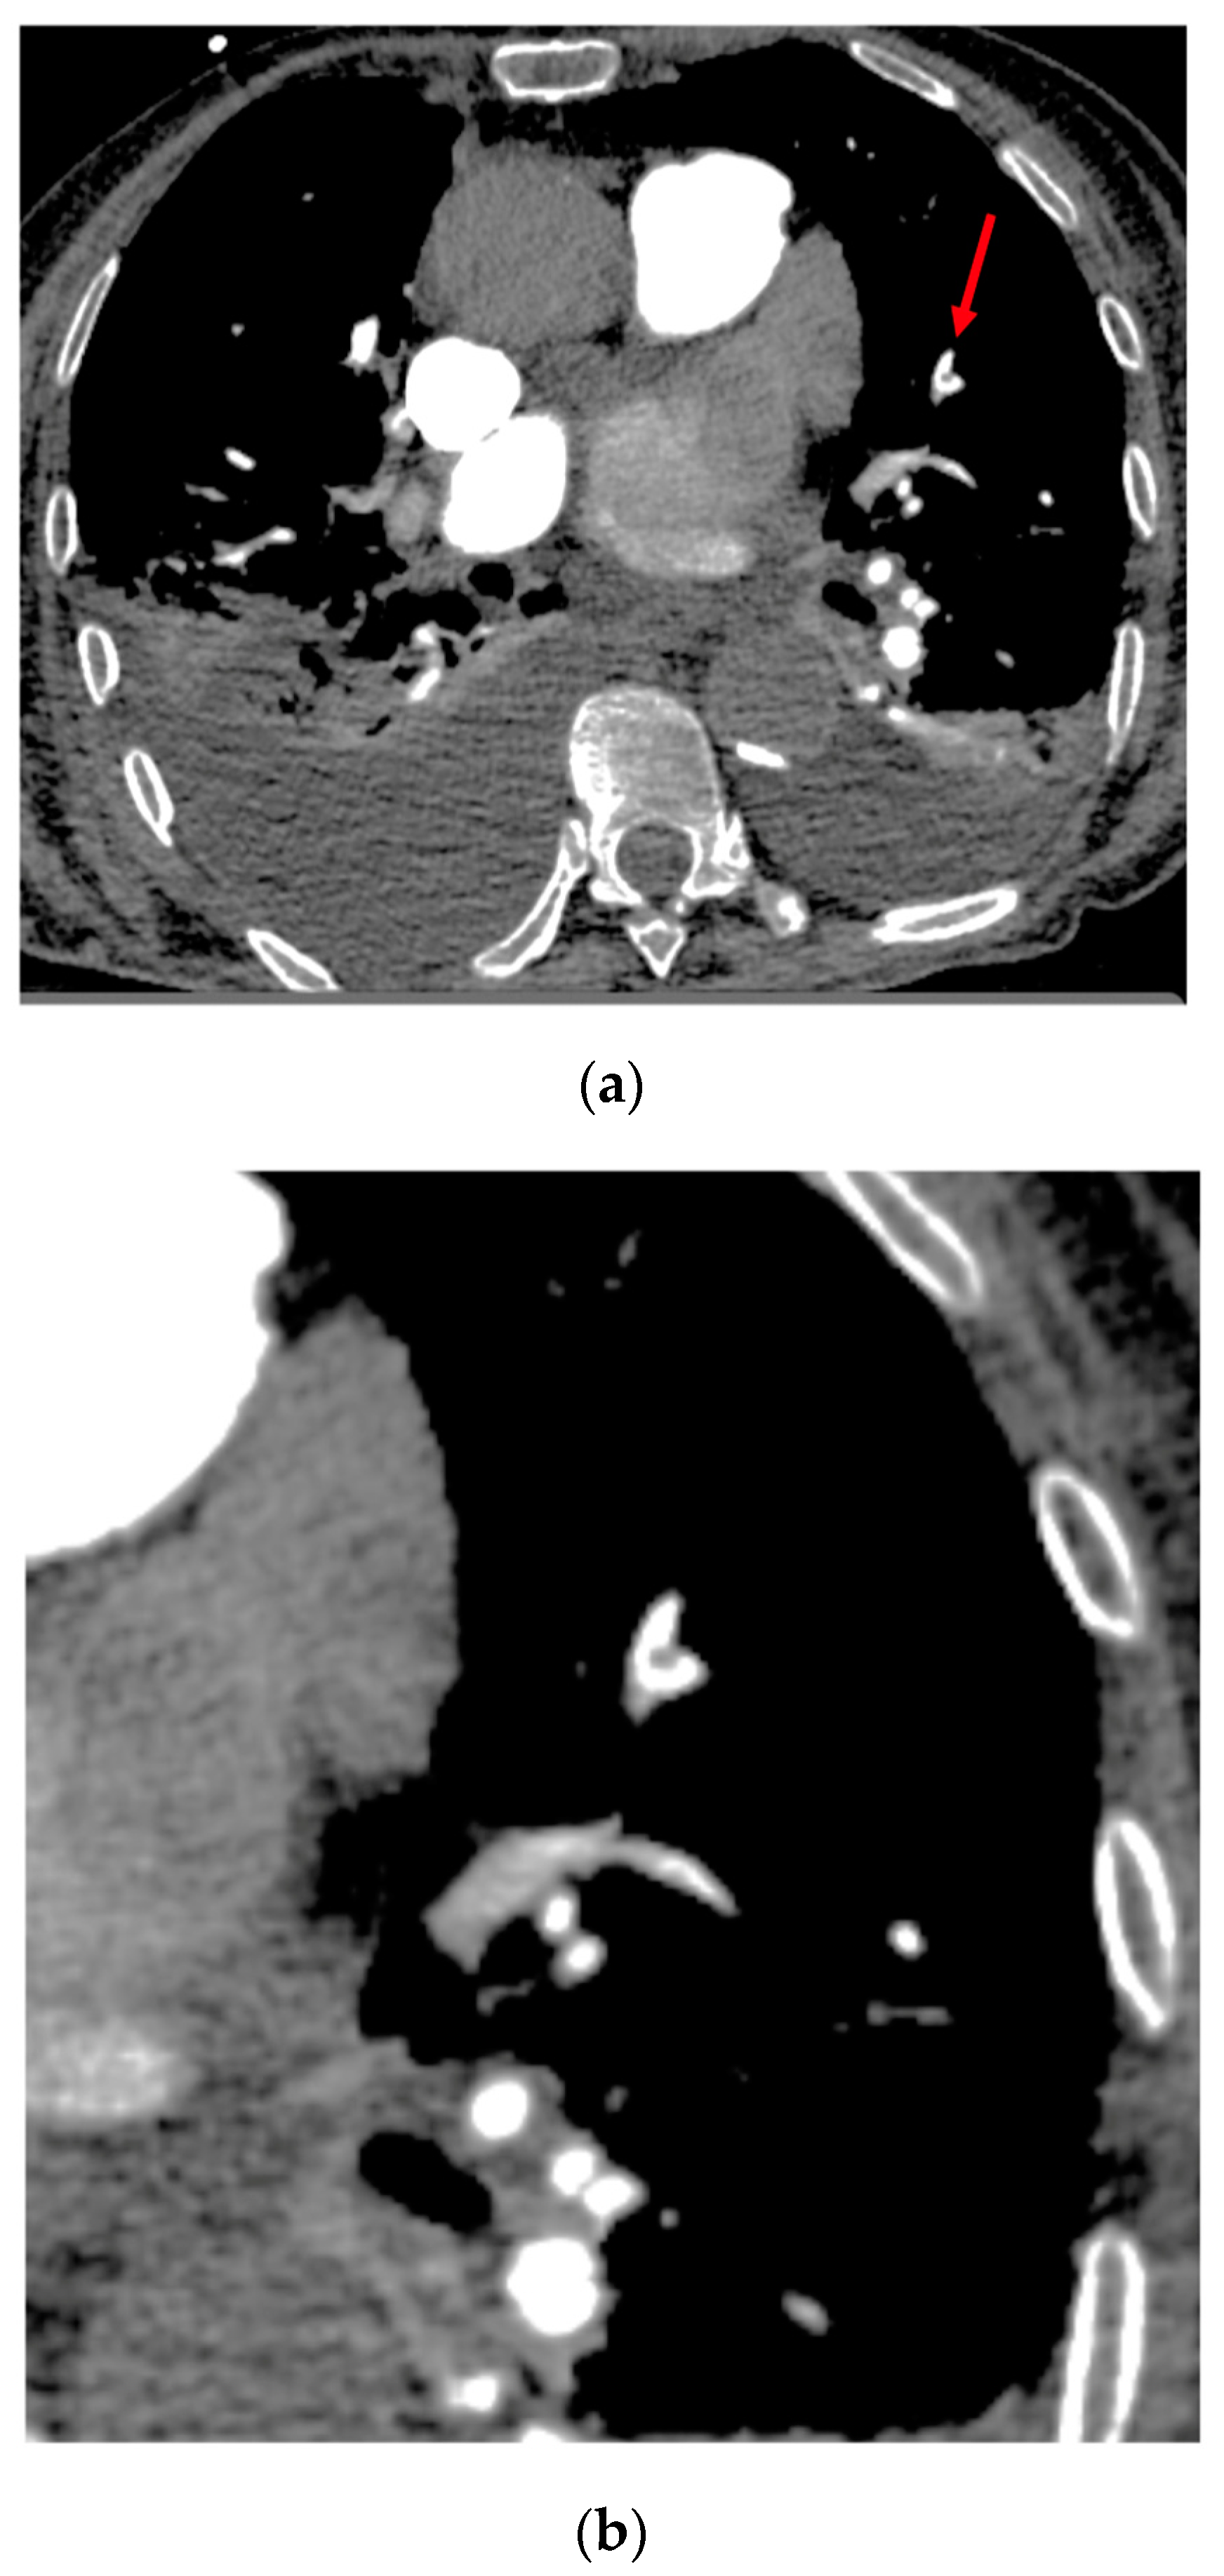

There were 16 FNs with a miss rate for PE of 8.6% (16/186 positive cases). Among them, six corresponded to small chronic PEs. The location and cause of the other FN cases are reported in Supplementary Materials—Table S2. Among these 16 FN cases, three were a cause of disagreement between the radiologists in charge to provide the ground truth, with huge difficulty to visualize the clots on the images. Several missed PEs were at the limit of subsegmental arteries and close to the partial volume effect artifacts (Figure 3).

Figure 3.

Case of the false negative response of the algorithm in the left upper lobe. Top (a): Axial image showing excellent opacification of pulmonary arteries. The red arrow shows the small filling defect within the termination of the segmental artery just close to the origin of subsegmental arteries. Note the presence of bilateral pleural effusion. Bottom (b): Axial image targeted on the left lung illustrating the presence of PE.